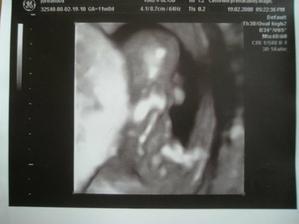

Tánička

Naša princeznička sa narodila 05.09.2008, presne deň pred termínom. Vážila 3580g a merala 51cm- proste modelka...